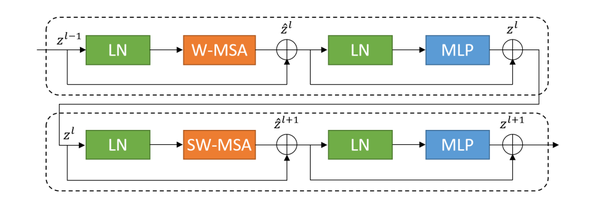

Distinguishing itself from traditional modules, the concept of a movable window is introduced into the improved network units. As shown in Figure 4, the structure diagram of a basic unit block is presented.

| Figure 4. Schema of swin transfomer block |

Each unit block within the network is configured to encompass layer normalization (LN), a multi-head self-attention mechanism (MSA), a residual connection, and two multilayer perceptrons (MLP). The block incorporates two types of attention mechanisms: a window-based multi-head self-attention mechanism (W-MSA) and a shifted window-based multi-head self-attention mechanism (SW-MSA) [12]. This design facilitates the employment of continuous unit blocks that utilize a movable window concept, enhancing the flexibility and effectiveness of the attention mechanisms in capturing varying spatial features.